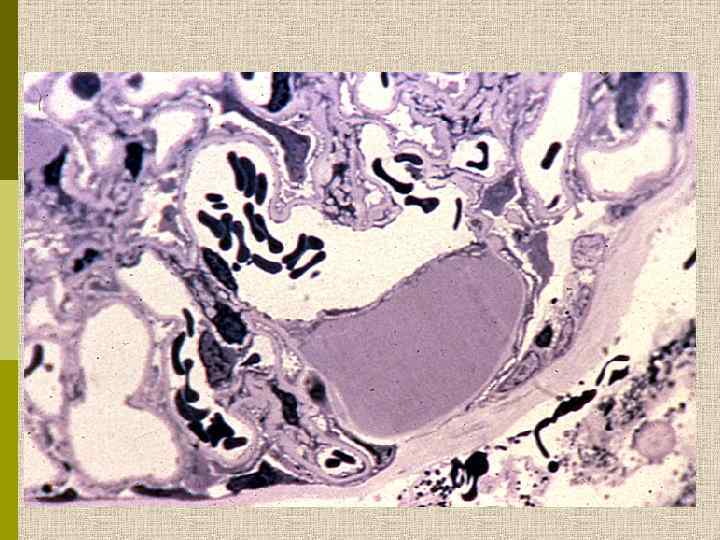

Узелковый гломерулосклероз (болезнь Киммельстиля. Вильсона). Узелки pink гиалинового материала в области петель клубочковых капилляров – значительное уширение мезангиального матрикса в резельтате неэнзиматического гликозилирования протеинов.

PAS Узелковый гломерулосклероз (болезнь Киммельстиля-Вильсона) у больного с длительным течением сахарного диабета. Выраженное утолщением артериолы – типичный гилиновый артериолосклероз, наблюдаемый при сахарном диабете.

МОРФОЛОГИЧЕСКИЕ ИЗМЕНЕНИЯ ПРИ ДИАБЕТИЧЕСКОЙ НЕФРОПАТИИ Основные варианты - диабетический гломерулосклероз с узелками Kimmelstiel-Wilson - диффузный мезангиальный гломерулосклероз Характерные признаки Утолщение ГБМ; артериолярный гиалиноз; аневризматические капилляры; капсулярные капли; фибриновые шапочки; атрофия канальцев; инфильтрация, расширение и склероз интерстиция; линейные отложения иммуноглобулинов